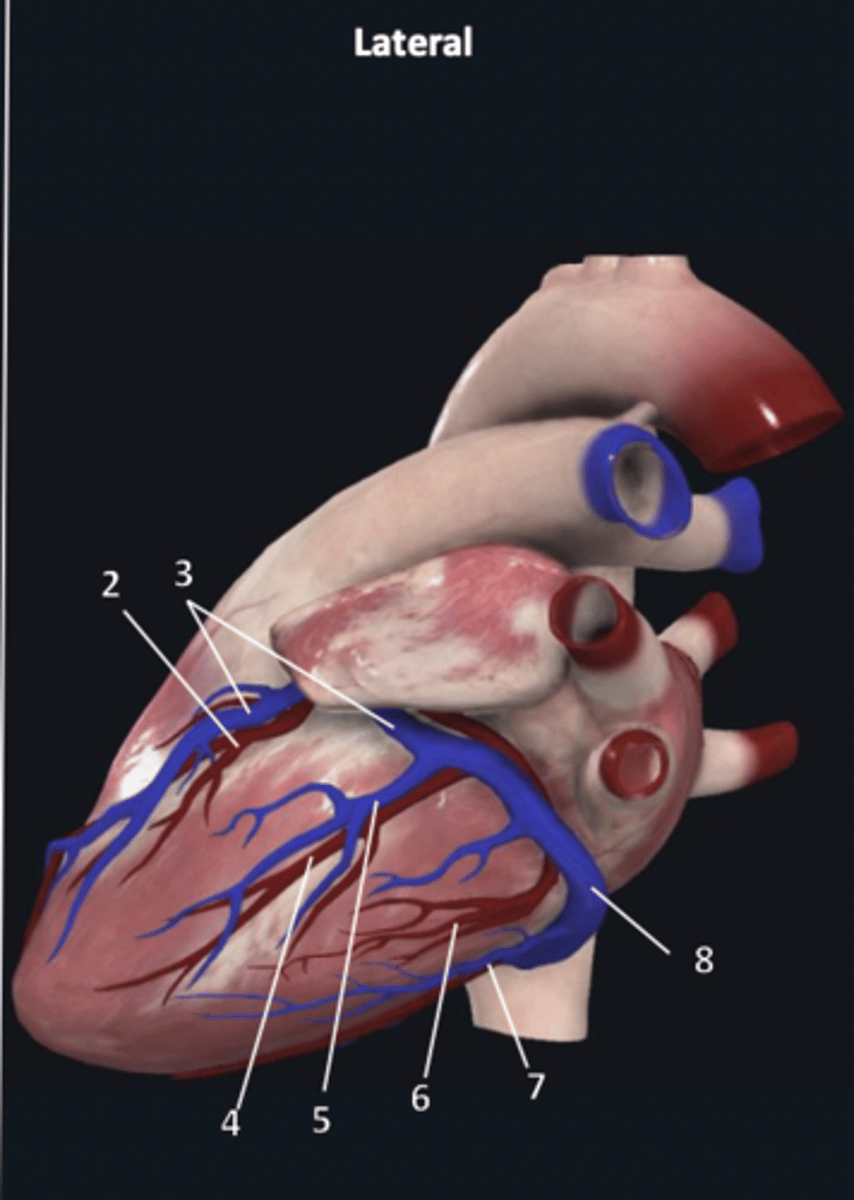

right coronary artery

1

left marginal artery

4

left marginal vein

5

posterior left ventricular artery

6

posterior vein of left ventricle

7

coronary sinus

8

right coronary artery

1 (red)

great cardiac vein

3

posterior left ventricular artery

6

posterior vein of left ventricle

7

coronary sinus

8

right posterolateral artery

9

middle cardiac vein

10

posterior interventricular artery

11

right marginal artery

12

small cardiac vein

13